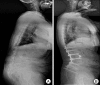

Results: Following surgery, lumbar lordosis increased from -14.1 degrees +/- 20.5 degrees to -46.3 degrees +/- 12.8 degrees (p < 0.0001), and the C7 plumb line improved from 115 +/- 43 mm to 32 +/- 38 mm (p < 0.0001). There were 16 surgery-related complications in 8 patients; 3 intraoperative, 3 perioperative, and 10 late-onset postoperative. The prevalence of proximal junctional kyphosis (PJK) was 23% (3 of 13 patients). However, clinical outcomes were not adversely affected by PJK. Intraoperative blood loss averaged 2,984 mL. The C7 plumb line values and postoperative complications were closely correlated with clinical results.